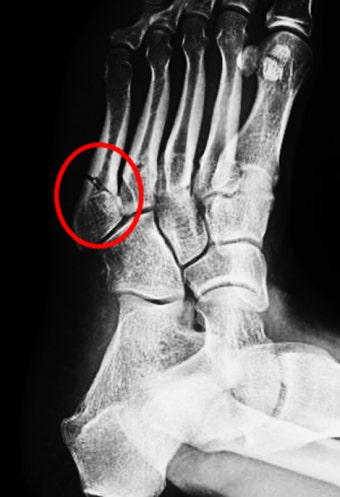

① 중족골 골절

발등 부분에서 흔합니다.

특히 5번째 중족골 골절은 매우 흔한 부상입니다.

① X-ray 검사

가장 기본적인 검사입니다.

의사는 검사 결과를 통해 골절 위치와 정도를 판단합니다.